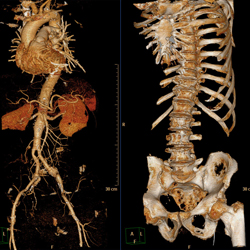

Gefäßdiagnostik

CT

Körperstammgefäße:

• Intracerebrale Gefäße

• Halsgefäße (Carotiden, Vertebralarterien)

• Thorakoabdominal

• Beckenbeingefäße

• Aneurysma

• Verschluß